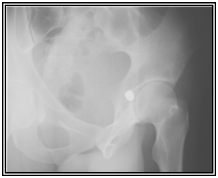

A 32 old male presented with a single gunshot wound to the right suprapubic area, with no exit. Radiographs revealed a bullet that appeared to be lodged in the left hip joint (Figures 1) A CT scan (Figures 2) and cystogram showed no associated injuries, with the bullet tract entering the quadrilateral surface of the left hip and the bullet buried in the posterior acetabular wall.

Figure 1 Radiographs at first presentation showing a bullet that appeared to be lodged in the left hip joint.

Figure 2 CT scan showed the bullet buried in the posterior acetabular wall.